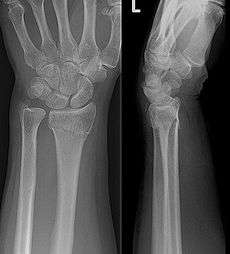

![]() Colles fracture on X-ray | |

Diagnosis may be evident clinically when the distal radius is deformed but should be confirmed by X-ray. The differential diagnosis includes scaphoid fractures and wrist dislocations, which can also co-exist with a distal radius fracture. Occasionally, fractures may not be seen on X-rays immediately after the injury. Delayed X-rays, X-ray computed tomography (CT scan), or Magnetic resonance imaging (MRI) will confirm the diagnosis.

Medical imaging

X-ray of the affected wrist is required if a fracture is suspected. CT scan is often performed to investigate the articular anatomy of the fracture, especially if surgery is considered. Investigation of a potential distal radial fracture includes assessment of the angle of the joint surface on lateral X-ray, the loss of length of the radius from the collapse of the fracture, and congruency of the distal radioulnar joint. Displacement of the articular surface is the most important factor affecting prognosis and treatment.